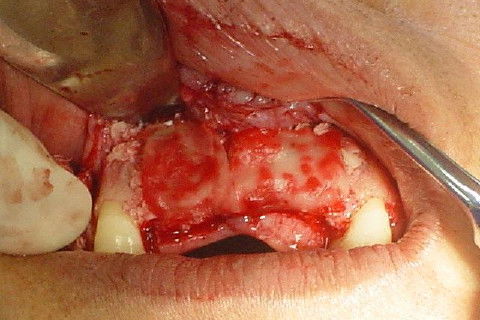

enxerto fixado

colocação de membrana reabsorvivel